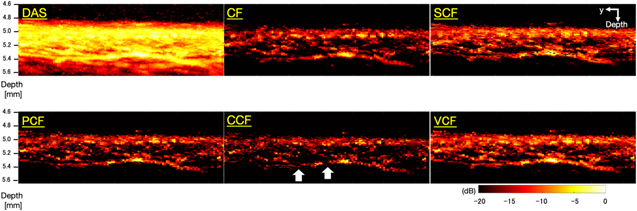

As one of the results of the phantom study, the images generated when the phantom was 5.0 mm away from the annular array are shown in Fig. 4. Figure 5 also shows the visualized phantom diameters in each MAP image of the phantom study visualized at all depths. Furthermore, Table I shows the sharpening ratio by applying each coherence factor method to the DAS beamformed signals.

Fig. 4. (Color online) The B-mode and C-mode images generated when the phantom was 5.0 mm away from the annular array.

In the B-mode image, the phantom image visualized with the DAS method was thicker than the original diameter, especially at depths of 5.0–6.5 mm, which was more than twice as thick as the original diameter of 100 μm. In contrast, all types of coherence factors showed a high effect of sharpening. However, in the case of the CCF method, the diameter of the phantom was thinner than 100 μm at all depths. At a depth of 7.0 mm, the diameter of the visualized phantom was thinner than the original diameter when several types of coherence factors were applied.

In the C-mode image, the phantom image visualized with the DAS method was thicker than the original diameter, which was more than twice as thick as the original diameter of 100 μm, similar to the B-mode. On the other hand, the effects of sharpening by all types of coherence factors were confirmed at all depths. The CCF method showed the highest sharpening effect as well as B-mode. However, the effect of sharpening by the SCF method was small than the other coherence factors. The width of the phantom visualized by C-mode tended to be thicker in the deeper position.

4.2. Microvascular imaging of human skin

Figure 6 shows the B-mode images generated by imaging microvessels with each method applied. Figure 7 shows closeup images of the area enclosed by the yellow square in each B-mode image. In the image generated by the DAS method, the entire signal intensity was high, thus the vascular structure was unclear. On the other hand, the images generated by applying several types of coherence factors to the DAS method showed that the entire signal intensity was suppressed and the structure of the blood vessels could be clearly seen. However, in the image generated by applying the CCF method, the visualized vessel structure was partially discontinued (the white arrow in Fig. 7).

Fig. 6. (Color online) The B-mode images generated by imaging microvessels with each method applied.

Download figure:

Standard image High-resolution imageFig. 7. (Color online) Magnified images of the yellow square regions in the microvessels B-mode images (Fig. 6).

Download figure:

In this study, we evaluated the effect of applying five types of coherence factors on DAS beamformed signals to improve the image quality by performing phantom study and microvascular imaging. Before discussing the characteristic effects of the five coherence factors tested in this study, we discuss the results of the phantom study and microvascular imaging of human skin.

5.1. Phantom study

In the phantom study, the improvement effect for image quality by applying the five coherence factors was evaluated by calculating the sharpening ratio of the phantom diameter at different imaging depths. In the B-mode and C-mode MAP images of the phantom study, the results suggested that the five coherence factors had a high effect of sharpening. However, in the B-mode MAP images at a depth of 7.0 mm, the phantom diameter visualized by applying the DAS method suddenly decreased and was confirmed to be around 100 μm. This may be attributed to the decrease in SNR of the PA signal in the deep region due to laser attenuation. In particular, the depth of 7.0 mm is deeper than the acoustic focal length of 6 mm, which is affected by both the influence of the laser attenuation and the decrease in the receiver sensitivity outside of the ultrasound focal length. Therefore, it is suggested that the phantom was not properly reconstructed due to the rapid degradation of signal reception sensitivity caused by these factors.

In the C-mode MAP images of the phantom study, the visualized phantom diameters were found to be larger than the true diameter at all depths and they were increased according to the depth. The reason for the lineally overestimation may be the linear degradation of the resolution and the measurement error due to the mechanical scanning. In the former case, the DAS method made the focal length variable, resulting in a linear change in the phantom diameter with a small  at deeper depths. In the latter case, the original phantom diameter is approximately three pixels in size, which means that the phantom is visualized at a depth of 5.0 mm with a spread of two or three pixels at both edges of the phantom. This indicates that the phantom was overestimated due to the measurement error caused by the mechanical scanning.

5.2. Microvascular imaging of human skin

In microvascular imaging of human skin, we qualitatively and quantitatively evaluated the effects of applying five coherence factors to improve the image quality by calculating the sharpening ratio, CR, and CNR. In the same way as the phantom study, it was confirmed that the five coherence factors had a sharpening effect on the target vessel in the C-mode MAP images. The CR increased in the four coherence factors applied images and suggested an improvement in image quality except for the CF.